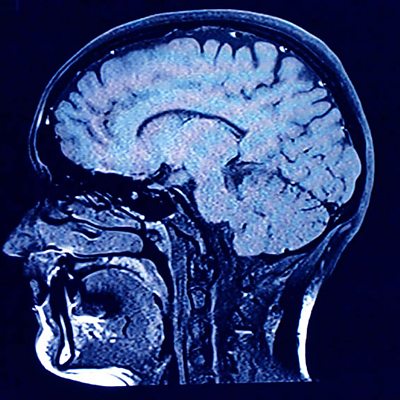

Chris Nowinski, who's an expert in head injuries in athletes, describes the lasting impact concussion has had on him and other players in contact sports.